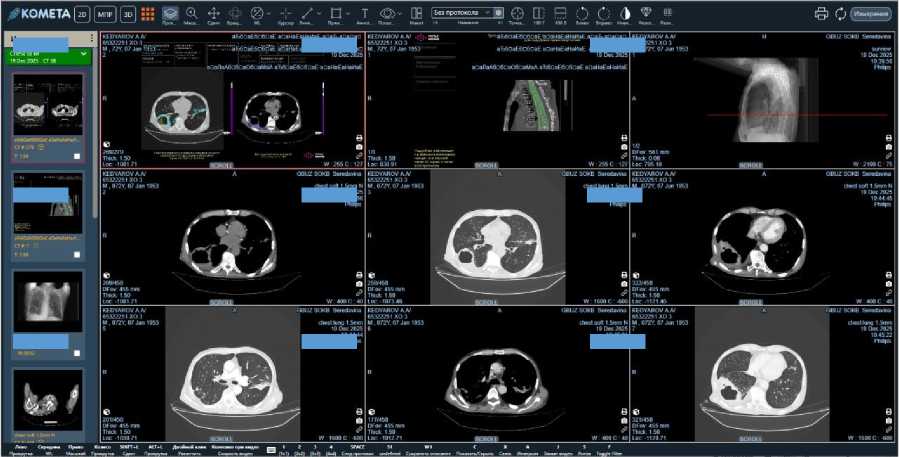

При организации и проведении ТМК по профилю «Торакальная хирургия» одним из ключевых элементов взаимодействия является возможность удалённого просмотра рентгенологических изображений. В настоящее время на территории Самарской области в рамках единой государственной системы здравоохранения функционирует Центральный архив медицинских изображений (далее – ЦАМИ) с системой просмотра «Комета», ко которому под- ключены 294 аппарата по модальностям Рентген, КТ, МРТ. По состоянию на 31.12.2025 года в ЦАМИ хранится 8 975 866 исследований. В подавляющем большинстве ТМК (132 случая / 95,6%) проведение консультации было обеспечено возможностью визуального просмотра диагностического изображе-ния/исследования в «Комете», что, безусловно, способствовало высокой доступности и качеству оценки данных (рис. 2).

Рисунок 2. Компьютерная томография пациента К., 72 лет. Острый абсцесс нижней доли правого лёгкого. Двусторонняя полисегмен-тарная деструктивная пневмония

Figure 2. Computed tomography of patient K., 72 years old. Acute abscess of the lower lobe of the right lung. Bilateral polysegmental destructive pneumonia